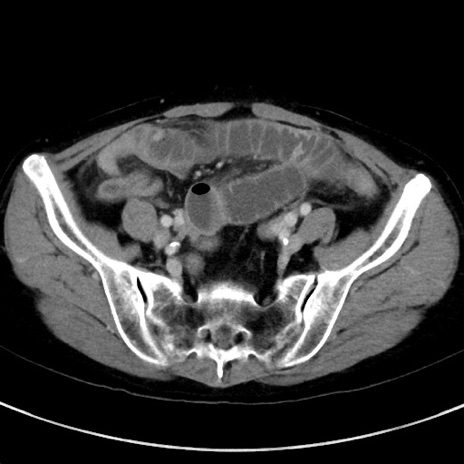

症例23(横断像)

【症例】70歳代女性

【主訴】下腹部痛・嘔吐

【現病歴】2日前より腹痛あり。昨日嘔吐あり。症状改善しないため来院。

【既往歴】胃GISTに対して胃部分切除後。

【身体所見】BT 37.1℃、BP 128/77mmHg、腹部:平坦・軟、下腹部に圧痛あり。

【データ】WBC 10200、CRP 0.31